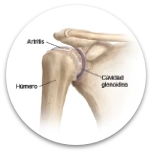

Para el dolor crónico en patologías como: Tendinitis, epicondilitis lateral, bursitis, fascitis plantar, entre otros.

Ayuda como: Antiage y rejuvenecimiento articular y Profilaxis deportiva. Mejora los síntomas de la Condromalacia y artrosis.